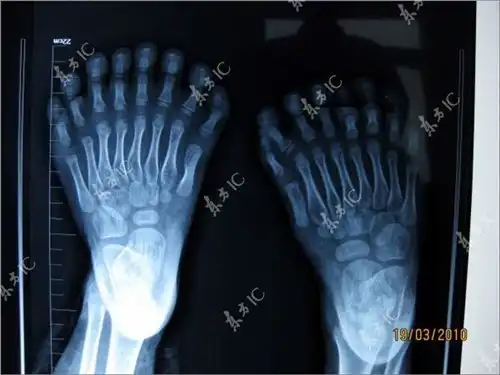

У шестилетнего ребенка 15 пальцев на руках и 15 на ногах. На каждой руке мальчика срослись по три пальца. Вчера ему должны были сделать операцию по удалению лишних конечностей. Ребенку поставлен диагноз «полидактилия» (многопалость), который представляет собой генетическую мутацию.